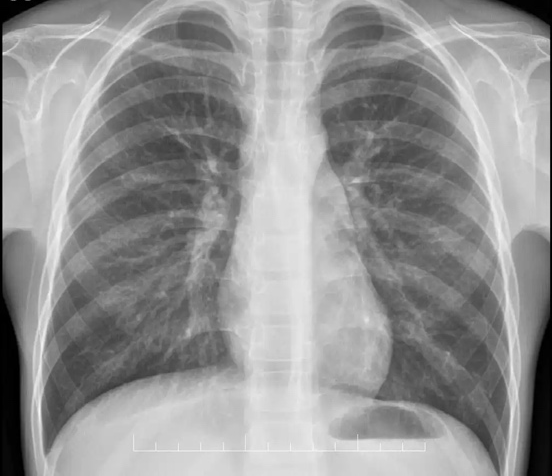

纵隔的胸腔特殊的解剖区域,狭小而又重要,在有限的空间里容纳了心脏、大血管、气管、食管、膈神经、迷走神经等重要的器官和机构,无论哪个器官、结构被肿瘤侵犯,均会导致非常严重的后果,而在其侵犯这些重要器官、结构之前,患者常常没有任何症状,甚至体检都没有发现。常规的体检一般只进行胸部 DR 检查,也就是我们常说的胸片。胸部 DR 成像特征为二维重叠影像,而纵隔内心脏、大血管等器官与肿瘤的的重叠效应,常常使纵隔肿瘤难以发现。虽然纵隔的空间狭小,其区域却具有很大的延展性,薄弱的纵隔胸膜、「大」器官的推挤耐受性以及多数肿瘤生长的缓慢性,使得患者常常没有症状,而到肿瘤压迫效应明显被发现时,肿瘤常常已十分巨大了,这也给治疗带来了困难和挑战,甚至使患者错过了手术的机会。

纵隔分为前、中、后三个区域,不同位置的纵隔肿瘤类型和症状各有不同。前纵隔位于胸骨后方,因幼年期存在的胸腺随年龄增长而逐渐被吸收,前纵隔空间较大,前纵隔肿瘤可轻松「鸠占鹊巢「,患者常常仅有轻微的胸部不适、疼痛,随着肿瘤逐渐长大,压迫心脏、大血管后患者才逐步表现出胸闷、气紧等症状,继续生长的肿瘤甚至可能侵犯上腔静脉系统导致」上腔静脉综合征「从而引起严重后果,部分胸腺瘤患者也会因」肌无力「作为首发症状。常见的前纵隔肿瘤包括:胸腺肿瘤、生殖细胞肿瘤、畸胎瘤、淋巴瘤、肉瘤等,不同的肿瘤治疗策略不尽相同,年轻患者的纵隔肿瘤常常恶性程度更高、生长更快。相较于前纵隔,纵隔的空间更为狭小,患者也常常更早出现压迫症状,如呼吸困难、吞咽梗阻、心脏压迫感等。常见的中纵隔肿瘤包括前肠囊肿、心包囊肿、血管淋巴管瘤等,以良性肿瘤居多,但因其狭小的空间常常给手术带来困难。后纵隔肿瘤因可以突入胸腔生长,所以压迫效应不明显,常常是偶然被发现,十分巨大的肿瘤可能因压迫肺部而导致呼吸症状。常见的后纵隔肿瘤包括神经源性肿瘤和囊肿性病变,其中婴幼儿的神经源性肿瘤常常恶性程度非常高。